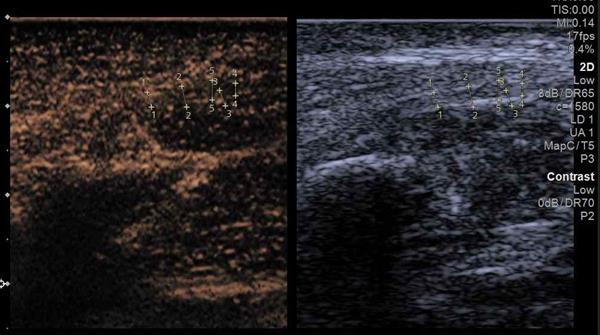

在此基础上,团队进一步为小彭实施超声造影检查。通过静脉注射造影剂,实时动态追踪腓总神经周围的微循环灌注情况。造影图像显示,神经周围微泡信号迅速增多,卡压点近端出现了明显的高灌注表现,提示该区域存在活跃的炎性反应,并伴有新生血管形成。弹性成像和超声造影的联合应用,实现了组织力学特性与微循环功能状态的多维度评估,精准判断出神经卡压所处的病理阶段,为后续治疗提供了关键的依据。

超声造影进一步评估受压的腓总神经血流情况

超声造影图像,清晰显示卡压点/损伤区域的异常血流灌注(亮点)